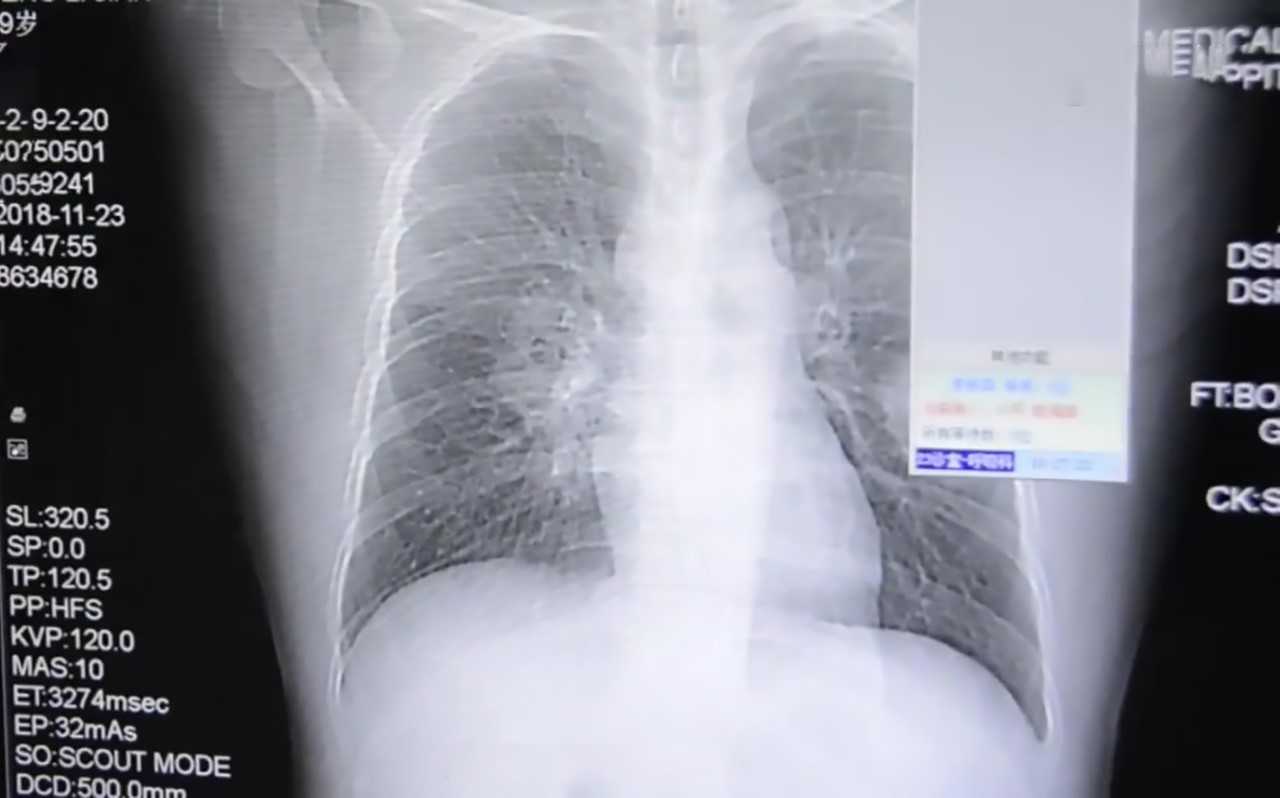

▼醫生見狀為他做了詳細的檢查,經肺部穿刺作檢測,發現他的肺部被真菌侵入。這是怎麼回事呢?在醫生的詢問下,他才表示,自己有一個怪癖,那就是每天下班回家後,都會把臭襪子脫下來聞一聞。他經常熬夜照顧小孩,免疫力下降,再加上壞習慣,這才導致身體不適。

▼醫生表示,患有腳癬的人穿過的鞋、襪很容易滋生真菌。幸好那名男子就醫比較早,並確定了原因,這才逐漸康復。肺部被真菌影響太嚴重,如果沒有及時發現的話,後果非常嚴重。